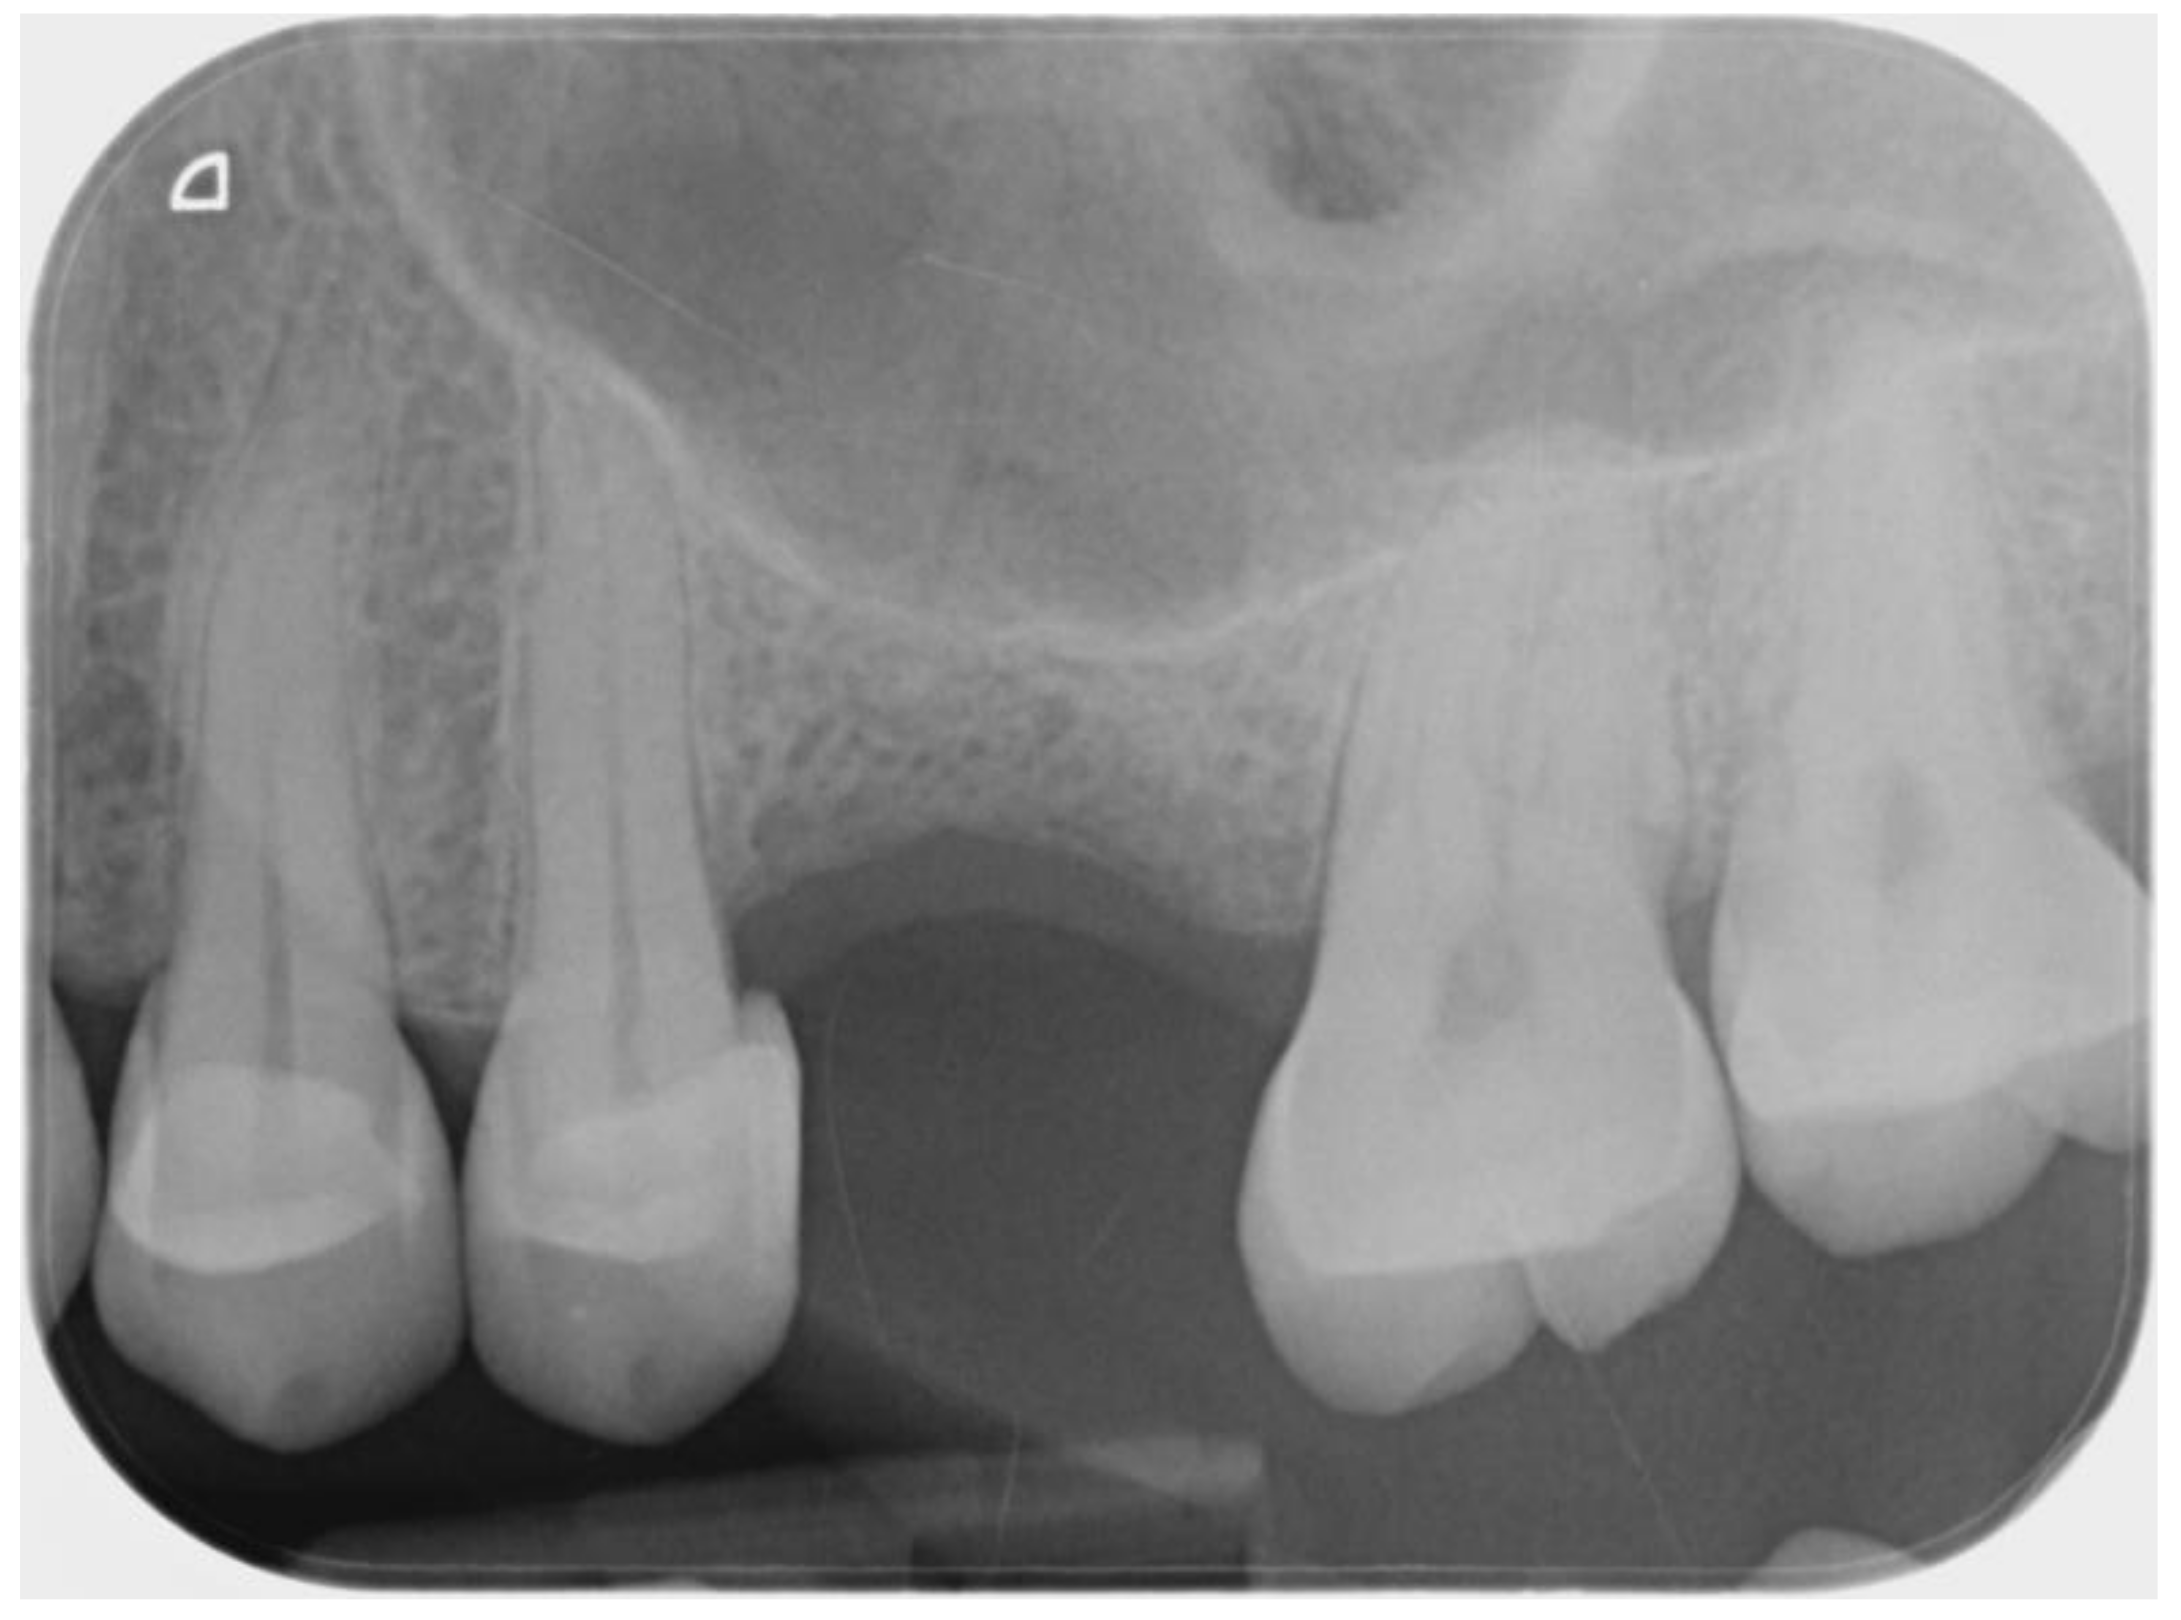

2.1. Planning

2.2. Surgical and Prosthetic Procedure